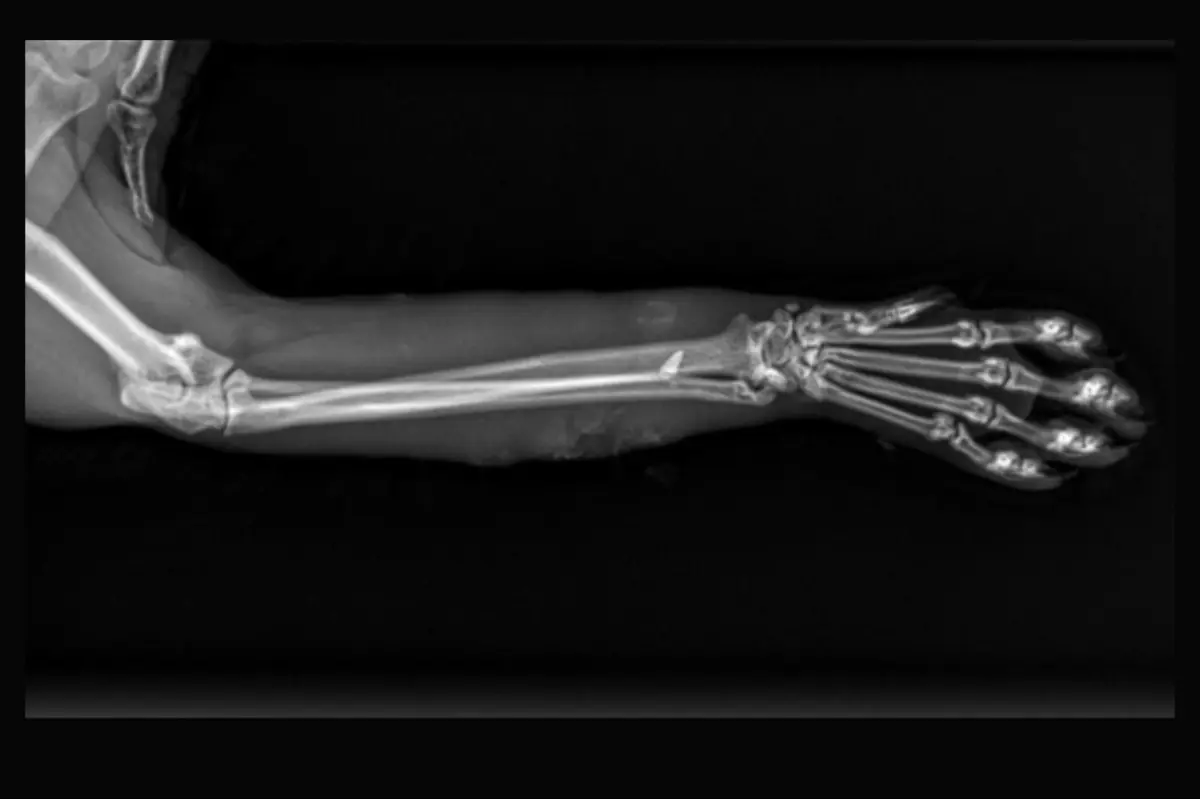

Mačky, ktoré sa pohybujú voľne po okolí, čelia mnohým nástrahám. No to, čo sa stalo jednému kocúrovi v Bystrici, presahuje hranice pochopenia. Podľa majiteľky ich miláčik prišiel domov zranený, s viditeľnou bolesťou. Veterinárne vyšetrenie odhalilo šokujúci nález - v jeho labke sa nachádzal brok. Niekto na mačku vystrelil.

„Zdravím, chcela by som Vás všetkých upozorniť na očividne mentálne postihnuté indivíduá, ktoré strieľajú po mačkách. Náš kocúr sa vrátil zranený, rtg ukázal v labke brok… niekto po ňom strieľal. Nemám slušného slova,“ varuje ostatných na sociálnej sieti Kristína.